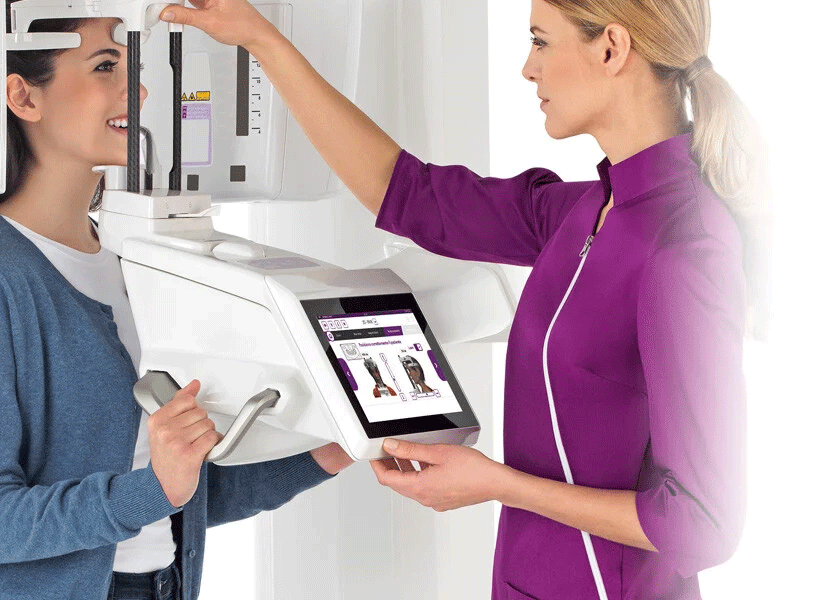

CONTRÔLE PAR iPAD

Hyperion X9 pro est équipé d’une interface graphique conviviale, également disponible sous forme d’application pour iPad, pour un contrôle simple et intuitif : en quelques simples étapes, vous pouvez choisir et paramétrer l’examen le plus approprié en fonction de l’intérêt clinique et anatomique.

CONSOLE TACTILE FULL TOUCH 10”

L’interface intuitive et les commandes directes accélèrent votre travail tout en offrant une expérience plus agréable au patient. Hyperion X9 pro est caractérisé par sa simplicité d’utilisation et la rapidité de ses procédures, comme le choix de vos programmes prédéfinis directement depuis la page d’accueil. L’interface de la console vous donne des indications précises sur le bon positionnement du patient en fonction du protocole sélectionné.